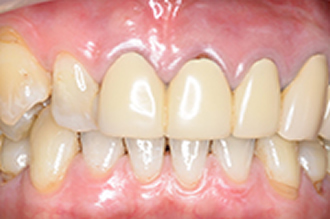

症例2

患者さんは60代男性 以前入れた保険の歯が色が変わって歯ぐきもやせたので白くしたいと希望術後

きれいに入って「こんなに保険の歯と違うのですか、入れて良かった」と喜んでおられました。

1本80000円(税別)

術前

術後